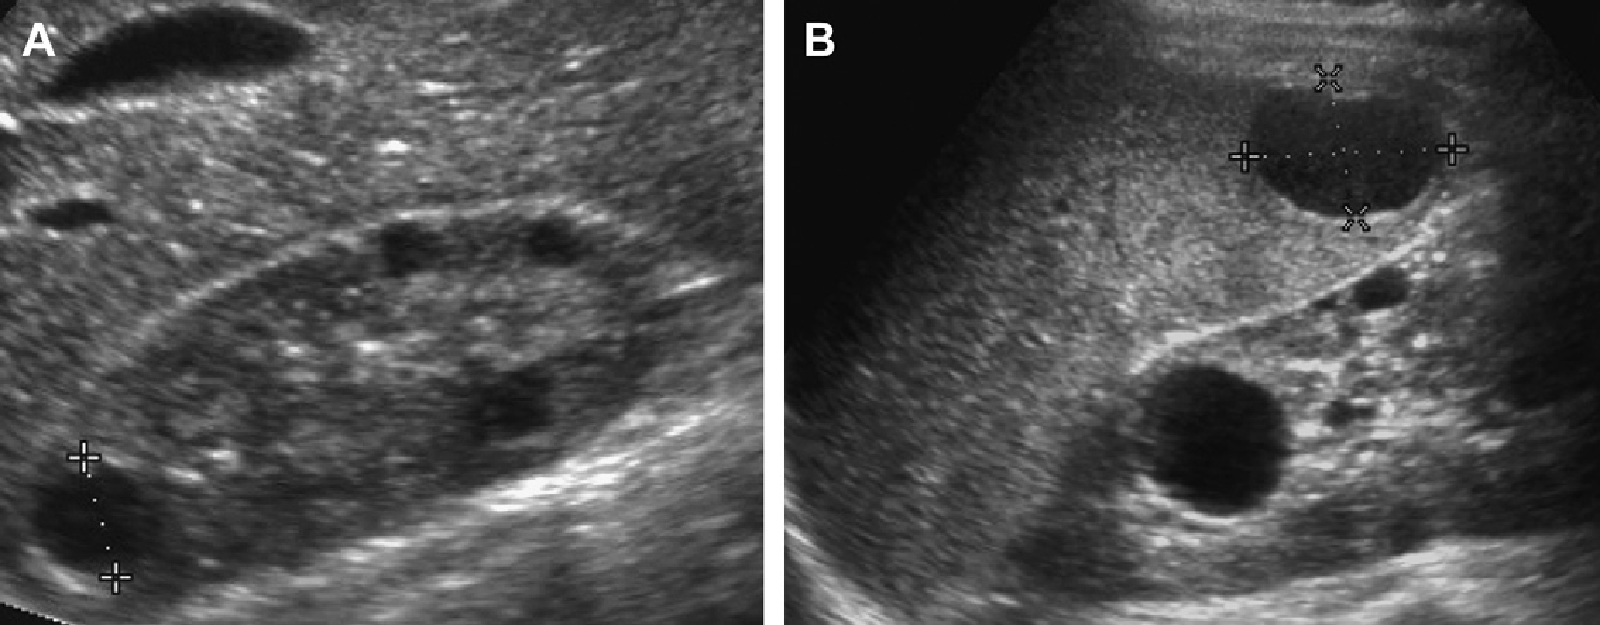

ЦДК сосудов почек: что это и как проводится